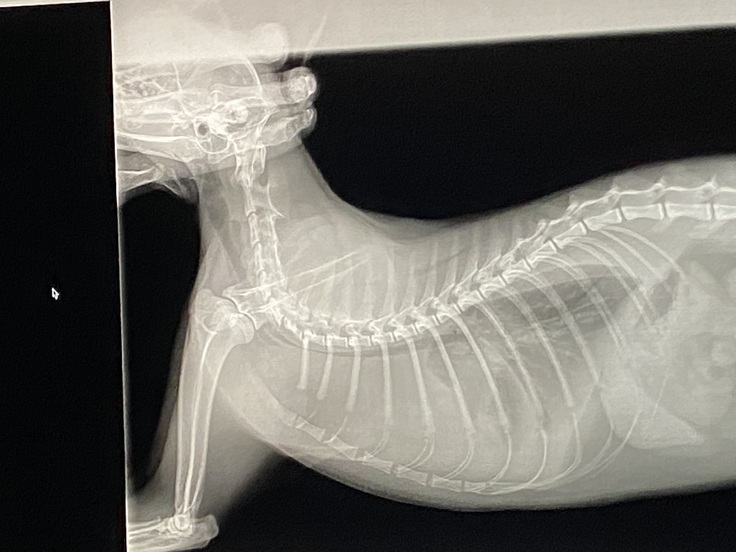

①画像は、6/14の朝呼吸が荒く、病院に行った時のものです。

獣医師から、胸水が溜まり、また、腫瘍により、気管が下から押され、とても苦しかったらだろうと説明がありました。